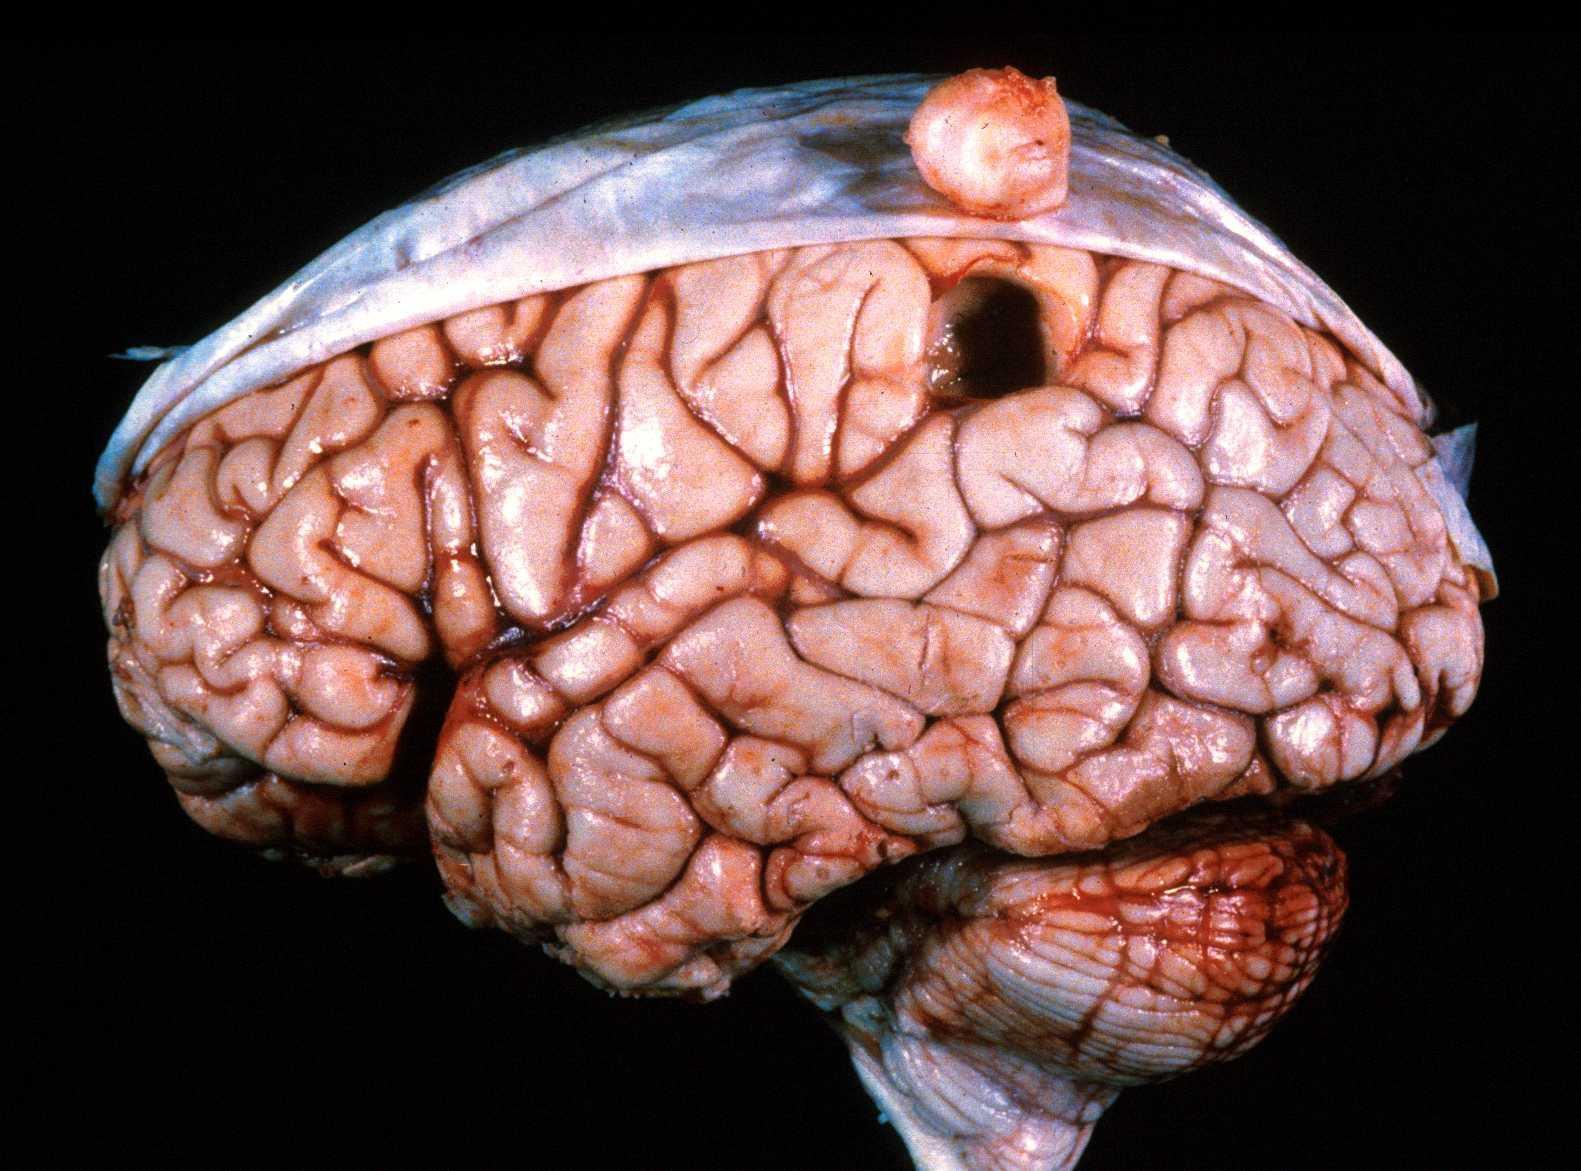

Ένα μηνιγγίωμα είναι ένας όγκος που δημιουργείται στις μήνιγγες, τις μεμβράνες που περιβάλλουν τον εγκέφαλο και το νωτιαίο μυελό. Τα περισσότερα μηνιγγιώματα είναι μη-καρκινικά (καλοήθη), αν και κάποιες φορές μπορεί να είναι και καρκινικά (κακοήθη).